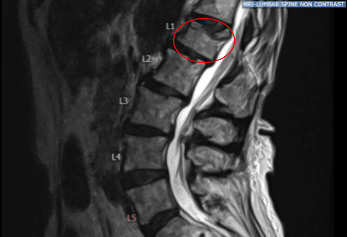

Case Study: L1 kyphoplasty with bipedicular access

An extremely pleasant patient with a past medical history of osteoporosis presenting with intractable back pain and a wedge compression deformity of the first lumbar vertebra. The physical exam showed tenderness of the right paraspinal region at L 5 and tenderness of the left paraspinal region at L 5.

Preoperative MRI showed hyperintense STIR signal change in L1 vertebra. After extensive discussion and the failure of nonoperative management, they were taken to the operating room for a L1 kyphoplasty procedure for pain control.